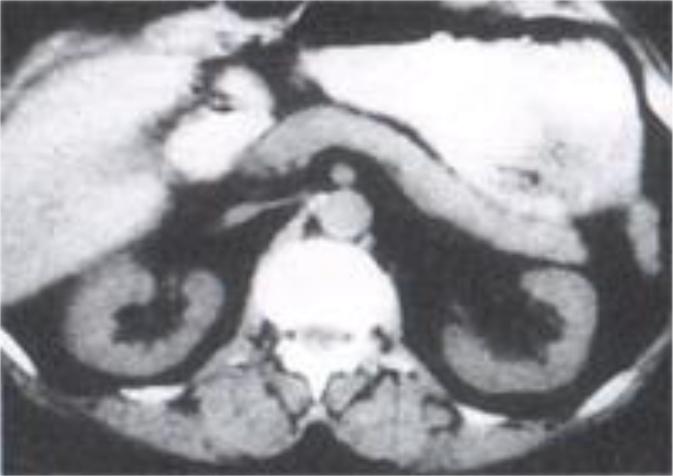

11)компьютерная томография: очаги некроза,

обыизвествлений и кист ПЖ

Компьютерная томография (норма):